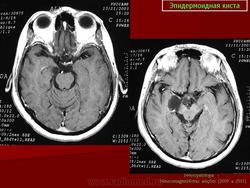

С 1985 по 2000 г.г. в НИИ нейрохирургии им. Н.Н. Бурденко обследовано и оперировано 78 больных с эпидермоидными кистами задней черепной ямки. Изучен клинический симптомокомплекс и КТ, МРТ картина эпидермоидных кист задней черепной ямки.

Качество оперативного лечения оценивалось изучением динамики неврологического статуса, данных КТ, МРТ, как до операции, так и после операции на разных его стадиях. Современные радиологические исследования и микрохирургическая техника полностью обеспечивает радикальное удаление эпидермоидных кист с хорошим после операционным результатом.

Эпидермоидная киста